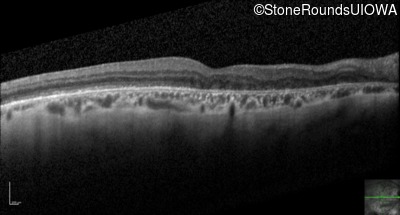

Optical Coherence Tomography - Right - 20/25 -2

Exemplar / OCT Stack